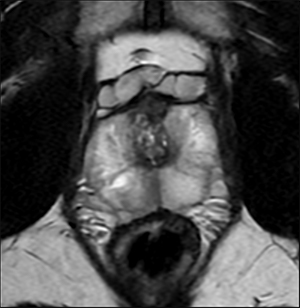

k空間データ全体に対して直接ディープラーニングアルゴリズムを適用し再構成する事でノイズ低減,画像の尖鋭度向上,トランケーションアーチファクトが低減する。従来の画像再構成とAIR™ Recon DLによる画像再構成との2つの比較画像を以下に添付する。

(1) ノイズ低減,画像の尖鋭度向上

従来の画像再構成 |

AIR™ Recon DLによる画像再構成 |